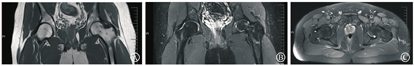

治疗上采取非甾体消炎药物(塞来昔布)+降钙素类药物(依降钙素注射液,每周2次,肌肉注射)+骨化三醇胶囊的联合治疗。患者两周复诊一次,每次复诊症状、体征均有明显好转。经过4个月治疗该患者于2018年9月复诊时症状体征完全消失,复查双侧髋关节MRI显示双侧髋关节在位,关节间隙存在,未见明显狭窄;左侧髋关节腔内见少量液体信号影,左侧股骨头颈部骨髓水肿基本消失(图3)。